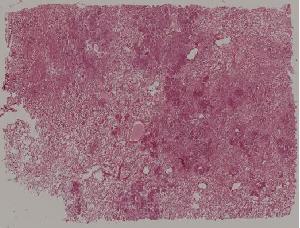

52. Lobular pneumonia

低倍视野